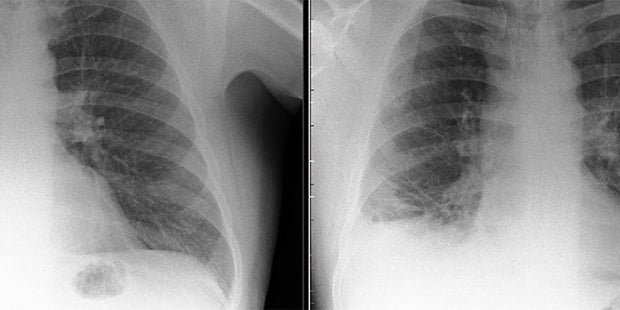

Ein 47-jähriger Brite ging mit starken Beschwerden ins Krankenhaus. Die Ärzte im Royal Preston Hospital hatten gleich einen schlimmen Verdacht: Die Symptome deuteten auf Lungenkrebs hin.

Als dann aber weitere Untersuchungen durchgeführt wurden, wurde schier Unglaubliches festgestellt. Auf einem Röntgen entdeckten die Ärzte in der Lunge einen kleinen, seltsamen Gegenstand.

Das kleine Ding wurde in Folge operativ entfernt und entpuppte sich als Teil eines Playmobils. Der 47-jährige Patient soll dieses als 7-Jähriger beim Spielen verschluckt haben. Über 40 Jahre lang hatte dies für ihn aber keine spürbaren Konsequenzen.

Der ungewöhnliche Fall wurde in BMJ Case Reports veröffentlicht.